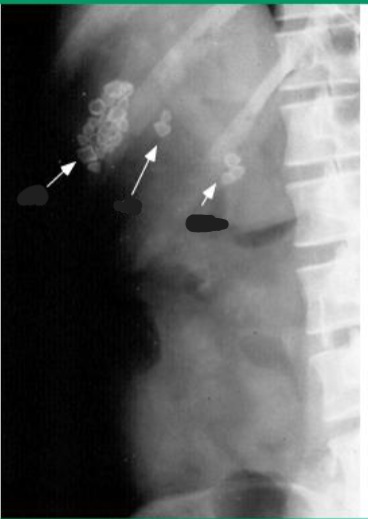

Abdominal Ultrasound most accurate if fasting >8 hrs, as stones are best seen in a distended GB filled with bile

Stones cast shadow + move around

Cholelithiasis

Calcified gallstones in gallbladder, cystic duct, and common bile duct